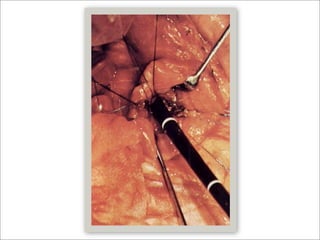

Abordaje por Coledocotomía

       Litos grandes ( > 1cm )

       Disección de la pared anterior del colédoco (15-20 mm)

       Evitar utilizar electrocauterio

   Corte longitudinal con bisturí (1-1.5 cm)

   Sutura para retracción de bordes de coledocotomía

   Colocar puertos adicionales de ser necesario

   Colocación sonda en T

    Ramas cortas

    Cierre del colédoco con sutura simple con material absorbible

    Nudos intra-corporeos

    Extracción de sonda a través de un puerto y se realiza Colangiograma

Abordaje por Coledocotomía  Litos grandes ( > 1cm )  Disección de la pared anterior del colédoco (15-20 mm)  Evitar utilizar electrocauterio  Corte longitudinal con bisturí (1-1.5 cm)  Sutura para retracción de bordes de coledocotomía  Colocar puertos adicionales de ser necesario  Colocación sonda en T  Ramas cortas  Cierre del colédoco con sutura simple con material absorbible  Nudos intra-corporeos  Extracción de sonda a través de un puerto y se realiza Colangiograma  ACS Surgery, Principles & Practice, WEB MD, 2006